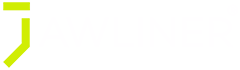

Nhìn vào ảnh trên, bạn có thể thấy khối xương Maxilla (màu vàng) liên quan tới sống mũi, phía dưới của 2 hốc mắt, 2 bên gò má và toàn bộ phần hàm trên. Nói cách khác, nó chính là khối xương quan trọng nhất tạo nên vẻ đẹp của chúng ta!

1. Vị trí của 2 hàm chuẩn hơn, đường jawline rõ nét, dài đẹp, vô cùng thanh tú

2. Mắt đẹp, quầng mắt ít hơn vì khi Maxilla bị tụt sẽ tạo khoảng lõm hốc mắt

3. Mũi cao, hỗ trợ đường thở dễ hơn.

Maxilla tụt thấp sẽ có nguy cơ:

1. Khó thở, thường xuyên ngáy to do miệng hở lưỡi rung tự do khi ngủ

2. Gù lưng mỏi vai do phải đỡ khuôn mặt bị tụt không cân đối

3. Xương gò má mất dần, mắt xệ, mặt bẹt, mũi tẹt